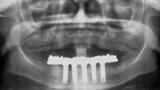

Fig. 7. Rx Pre-operatoria, Prótesis híbrida inmediata con 10 años de evolución y Rx Control a los 10 años.